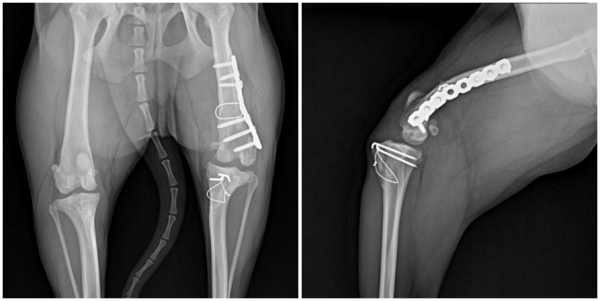

- 좌측 슬관절에서 슬개골 재탈구

- anatomic lateral distal femoral angle (aLDFA) 약 114°로 확인

- 슬개골 경화 및 주변 골증식체

- 관절 삼출 증가

- 십자인대 단열 소견 확인되지 않음

하쿠(가명)는 고랑성형술과 경골결절변위술·외측 연부조직 봉합술만으로는

교정이 충분하지 않았고 허벅지뼈가 안쪽으로 휘어진 변형까지 확인되어

이를 바로잡는 대퇴골 교정 절골술이 추가로 필요했습니다.